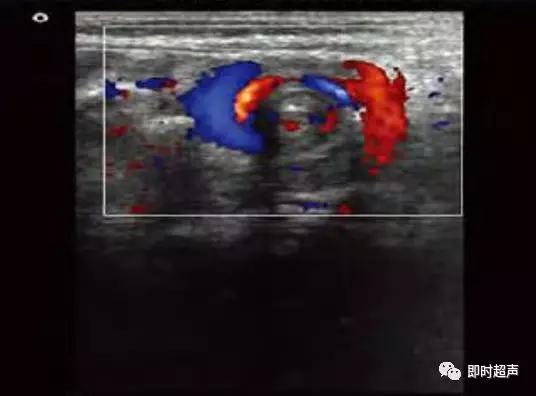

SMV连同所属的肠系膜和肠管围绕SMA发生顺时针旋转,超声横切面下呈现类似风暴引起的 “漩涡”征象

肠系膜动静脉位置异常,彩色血流漩涡征

肠系膜上动、静脉位置关系异常:AO IVC

CDFI:SMV围绕SMA旋转

- SMV/SMA位置逆转:SMV位 于SMA左 侧。

- Whirlpool征:SMV围绕SMA形成漩涡征象

- SMV扩张。

- 腹水。其中①或②为必备条件,其他为辅助征象。